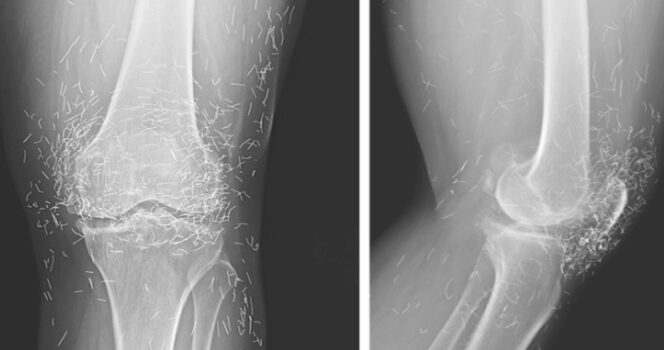

W związku z tym kobieta zdecydowała się na akupunkturę. Zgodnie z tym, jak opisano jej przypadek w czasopiśmie New England Journal of Medicine.

Akupunktura, znana od wieków metoda leczenia alternatywnego, polega na wkłuwaniu igieł w określone punkty ciała w celu złagodzenia bólu lub leczenia chorób. W tym przypadku igły wykonane ze złota, celowo pozostawiono w kolanach pacjentki w celu dalszej stymulacji.

Profesor ostrzegł również, że wbite igły mogą utrudniać odczytanie zdjęć rentgenowskich. „Igły mogą zasłaniać niektóre części anatomiczne” –powiedział Guermazi w 2013 roku.

Co gorsza, igły pozostawione w ciele mogą stwarzać zagrożenie dla przyszłych badań obrazowych. „Pacjent nie może poddać się rezonansowi magnetycznemu, ponieważ igły pozostawione w ciele mogą się przesunąć i uszkodzić tętnicę” – dodał Guermazi.